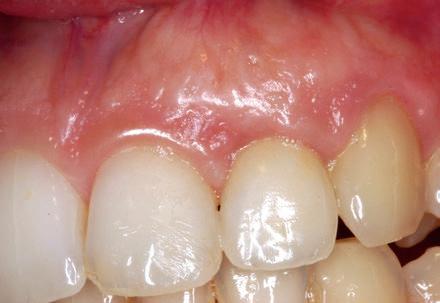

Mujer de 19 años remitida a nuestra consulta para tratar una dehiscencia de tejido blando que presentaba un implante localizado a nivel del 22 y que había sido colocado un año antes, debido a una agenesia. Esta paciente, había sido sometida durante su adolescencia a tratamiento ortodóntico. Los datos más relevantes de este caso son la presencia de un biotipo festoneado y fino y unas pequeñas retracciones en la encía marginal de 21 y 23 (pero no en el 22), así como

la existencia de dehiscencia ósea moderada en estos dientes. (Fig 13)

Para tratar la deshiscencia de tejido blando, se realizó un injerto de tejido conectivo submarginal asociado a un colgajo reposicionado (no desplazado) (Fig 14). En la g 15, se aprecia la cicatrización temprana con un buen sellado de la dehiscencia. La paciente

es remitida a su odontólogo de referencia y acude de nuevo a nuestra consulta nueve años más tarde. Lo curioso de lo ocurrido es que aunque el injerto fue ubicado en una posición submarginal, con los años sufre un cambio en su forma y volumen, desplazando a la encía en sentido coronal a nivel del 22 y cubriendo las pequeñas recesiones existentes en 21 y 23. (Fig 16) Lo llamativo de este caso es que el tejido blando ha cubierto parte de la corona del 22. Si bien guarda ciertas similitudes con el caso número 2, ya que ambos injertos tienen una ubicación

Fig 13: Año 1997. Mujer de 19 años que presenta una fenestración en el tejido blando, correspondiente a un implante colocado a nivel del 22. Se aprecia un biotipo extremadamente no y pequeñas recesiones en 21 y 23.

Fig 16: Resultado a los 9 años. El injerto, ha sufrido un remodelado, con un cambio en su forma y volumen. Curiosamente, el margen gingival que se había respetado, se ha desplazado en sentido coronal sobre la corona del implante, cubriendo las pequeñas recesiones existentes en 21 y 23. Compárese con la Fig nº 13.

submarginal, se presenta una diferencia sustancial que merece la pena remarcar. En el caso número 2, existía una recesión y el tejido blando se había remodelado sobre la super cie radicular expuesta. En este último caso, sin embargo, no existía una recesión, habiendo crecido el tejido blando sobre la corona del implante, otorgándole una corona clínica más corta que la inicial.